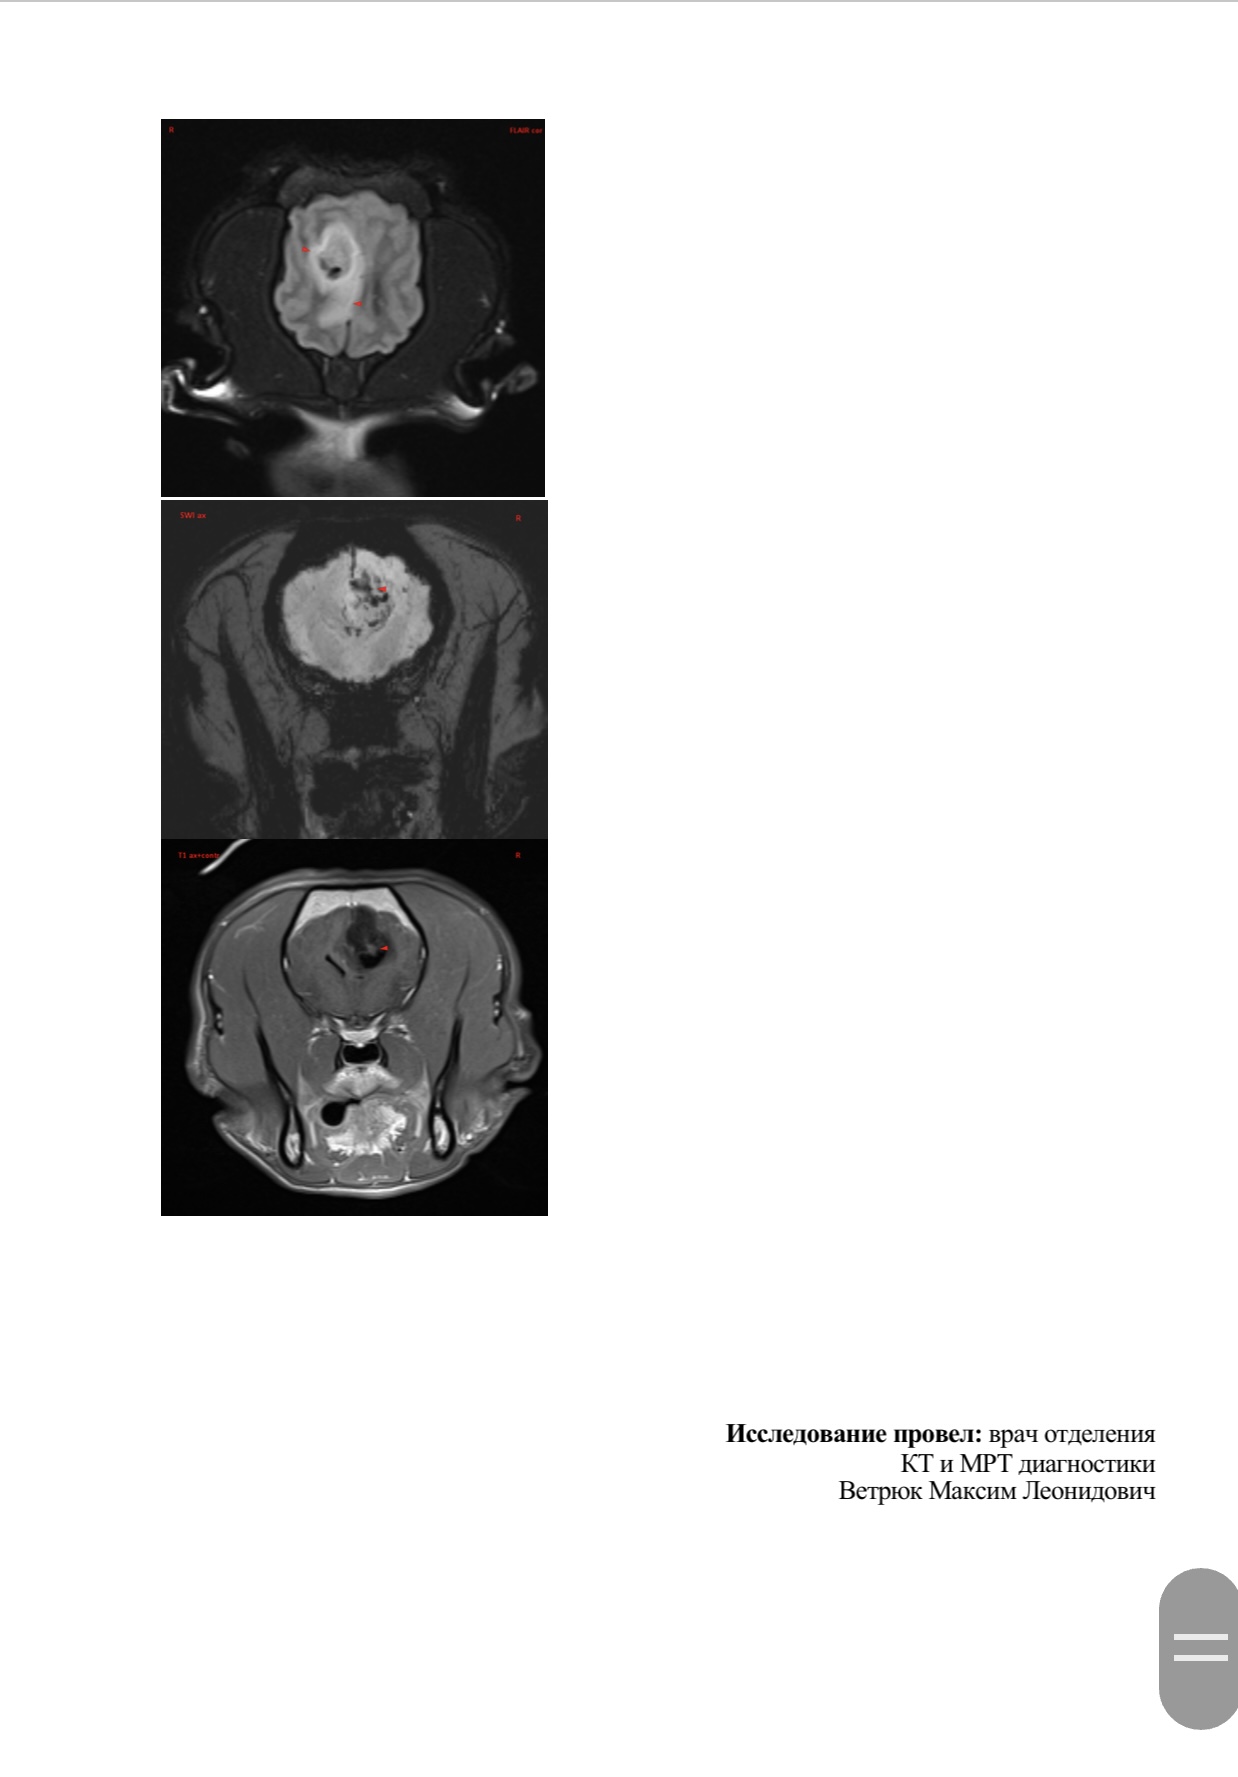

Вчера делали Марику МРТ в клинике Skolkovo Vet, если кому-то интересно, стоит чуть больше 12000₽. Результат неутешительный. Заключение:

МР-признаки новообразования в области лобной и теменной долей коры больших полушарий головного мозга справа, с очагами кровоизлияния и перифокальным отеком.

МР-признаки постсудорожных изменений.

Опухоль у моего мальчика(( она и вызывает судороги. Написала сегодня в вотс ап Хохлову, не знаю ответит ли, готова ехать к нему в клинику если он вообще принимает пациентов. К Дубовицкой попасть нереально, там очередь минимум на 1,5 месяца, есть онлайн консультация, стоит как и очный прием 7000₽, но ее рекомендуют скорее как второе мнение после очного осмотра у невролога. Рекомендовали еще Субботина из Белого Клыка, но увы, он по известным всем причинам с 2022 работает в вет клинике в Грузии. Продолжаю давать Кеппру и Габапентин